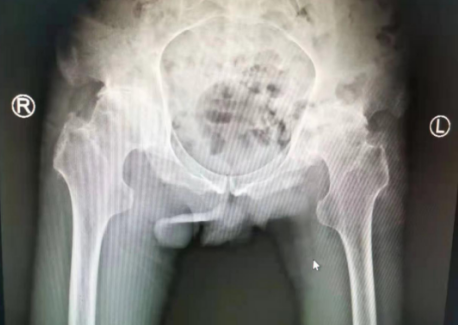

关节科蒋守海主任给吕师傅做了检查,吕师傅的左右髋关节内收外展、内外旋均不能;由于长时间坐轮椅,吕师傅的下肢肌肉已经开始萎缩,左下肢比右下肢短2厘米,摄片显示双侧骨头密度增高,双髋关节间隙狭窄,双髋臼缘及股骨近端见骨质增生,诊断为双侧股骨头无菌性坏死,强直性脊柱炎,左股骨近端陈旧性骨折。患者才32岁,如果要挽救髋部功能,必须进行髋关节置换手术。

术前

因为吕师傅身患两种“不死的癌症”,病情拖延时间久,比较复杂,张贯林副院长和蒋守海主任张玉帅陈强团队一起,进行了严谨周全的术前评估和分析,制订了万无一失的手术计划与步骤,在间隔一周的时间内,张院长和蒋主任手术团队为患者先后进行了两侧全髋关节置换手术。术中,手术团队以改良Gibson入路,切开阔筋膜,显露髋关节囊,切开,骨刀去除增生骨赘,脱出股骨头,摆锯截骨,取出坏死的股骨头,清理,依次安装髋臼假体、股骨柄、股骨头,测试髋关节活动稳定无脱位,透视全髋关节假体位置合适。手术很顺利、成功。